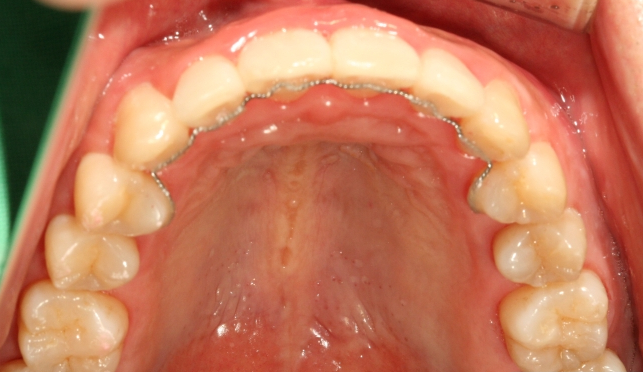

위에서 보았을 때 튀어나온 앞니가 들어간 사실을 확인할 수 있고요

이때 안쪽으로 들어가 있는 철사는

교정이 끝나면 하는 유지 장치 중 하나입니다.

교정이 끝나고 나서도 틀어지지 않도록 유지해 주는 장치입니다..